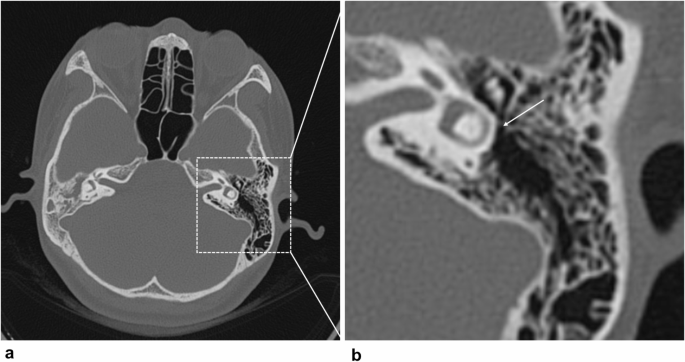

Based on the patency of the aditus ad antrum observed in axial CT images, patients were categorized into two groups: the aditus ad antrum group, indicating patency, and the aditus ad antrum group, indicating obstruction. Figure 3 presents axial CT images of the temporal bone demonstrating a patent aditus ad antrum. Conversely, Fig. 4 depicts preoperative CT imaging revealing complete obstruction of the aditus ad antrum.